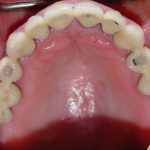

Case 6 – Upper Crowns / Lower Implants Makeover

- After